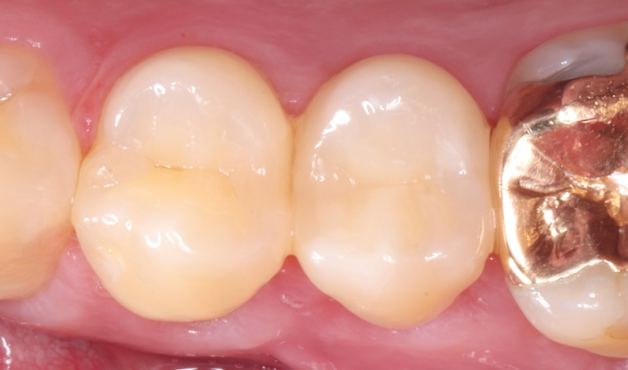

長期予後を見越した根管治療の症例

タップで写真の拡大ができます。

Before

After

主訴

症状はないが、治療が必要な箇所があればしっかり治療しておきたい。

治療内容

イニシャルトリートメント(根管治療・大臼歯)、ファイバーポストコア、セラミッククラウン

治療期間

3ヶ月

治療費用

352,000

治療の

リスク

根尖部透過像が完全に消失しない可能性があります。